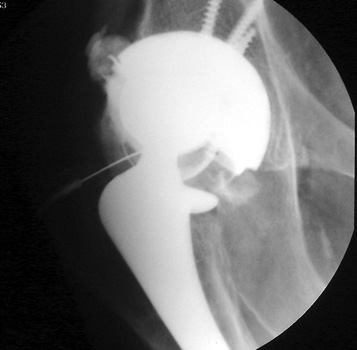

Polyethylene liner wear seen or radiograph and CT coronal reconstructed image. Note eccentric position of femoral head in cup